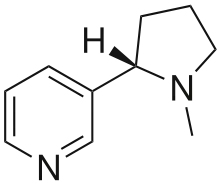

More recent classifications are based on similarity of the carbon skeleton (e.g., indole-, isoquinoline-, and pyridine-like) or biochemical precursor (ornithine, lysine, tyrosine, tryptophan, etc.).[5] However, they require compromises in borderline cases;[38] for example, nicotine contains a pyridine fragment from nicotinamide and a pyrrolidine part from ornithine[40] and therefore can be assigned to both classes.[41]

- "True alkaloids" contain nitrogen in the heterocycle and originate from amino acids.[43] Their characteristic examples are atropine, nicotine, and morphine. This group also includes some alkaloids that besides the nitrogen heterocycle contain terpene (e.g., evonine[44]) or peptide fragments (e.g. ergotamine[45]). The piperidine alkaloids coniine and coniceine may be regarded as true alkaloids (rather than pseudoalkaloids: see below)[46] although they do not originate from amino acids.[47]

| Polycyclic noncondensing pyridine derivatives | Nicotine, nornicotine, anabasine, anatabine [77][80] | ||